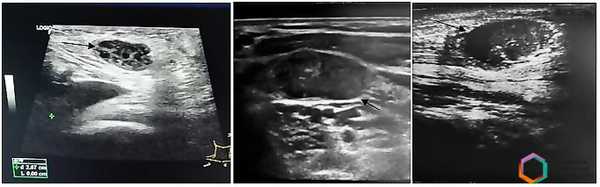

В 58 (38,2%) случаях было заподозрено метастатическое поражение лимфатических узлов. Измененные ЛУ имели размеры от 6 до 65 мм; 72,4% лимфатических узлов имели шарообразную форму, П/ПЗ2,0; 17,3% — неправильную форму в виде конгломератов. У 24 (41,4%) пациентов были выявлены единичные измененные лимфоузлы; у 34 (58,6%) — множественные. У 79,3% лимфоузлов отсутствовала дифференциация на кору и ворота; у 20,7% — ворота определялись в виде мелкого гиперэхогенного включения. 70,8% лимфатических узлов были гипоэхогенными (рис. 3); 12% — анэхогенными; 17,2% — неоднородную структуру с участками повышенной и пониженной эхогенности, с жидкостными включениями и кальцинатами (рис. 4).

В 31% случаев лимфатические узлы имели неровные, размытые контуры, что расценивалось как признак инвазии в окружающие ткани. В режиме цветового допплеровского картирования в 17,2% случаев визуализировались проникающие сосуды, выходящие за пределы пораженного лимфатического узла в окружающие ткани, что расценивалось как дополнительный признак инвазии. В 10,3% случаев была заподозрена инвазия в прилежащие сосуды, так как отсутствовала граница между сосудистой стенкой и пораженным лимфатическим узлом. При оценке кровотока в 75,9% пораженных ЛУ регистрировался смешанный тип.